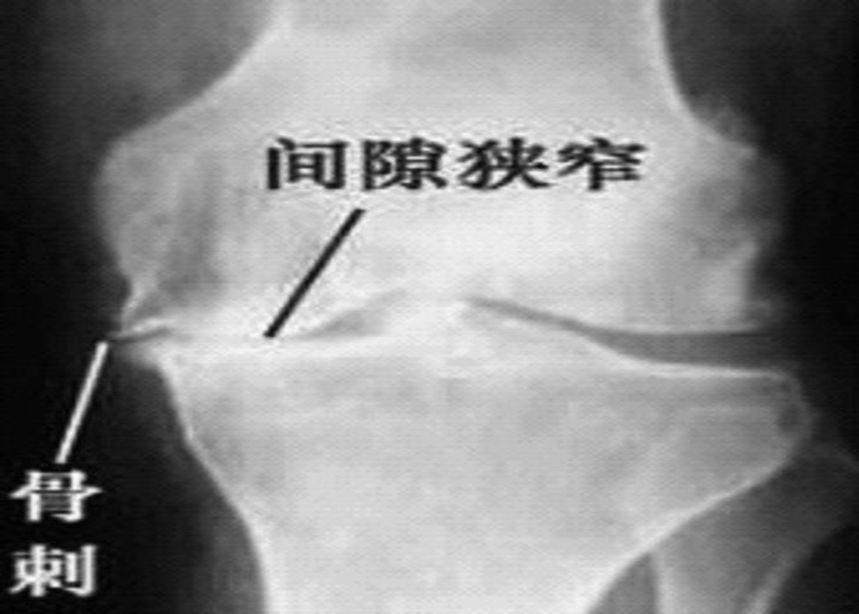

2、X线片(站立或负重位)示关节间隙变窄、软骨下骨硬化、和(或)囊性变、关节缘骨赘形成。

1、关节间隙变窄:成人膝关节间隙为4mm,小于3mm即为关节间隙狭窄,60岁以上的老人膝关节间隙为3mm,小于2mm为关节间隙狭窄。

2、软骨下骨板硬化:软骨下骨板致密、硬化,负重软骨下骨质内可见囊性改变。

3、骨赘形成。

软骨下骨板硬化